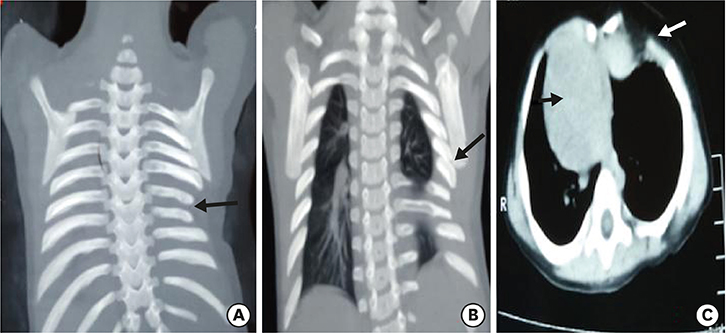

A plain radiograph chest X-ray (Fig. 1) was suspicious of bowel loops or stomach herniating into the left hemithorax. With a working diagnosis of congenital diaphragmatic hernia (CDH)/hiatus hernia, the patient was planned for emergency surgery. The patient was explored through a left subcostal incision. There was no diaphragmatic defect. Although the left diaphragm was higher up in position, it was normal, thick and muscular and not thin and redundant, as in diaphragmatic eventration. There was no paraesophageal or sliding hernia. The spleen was found to be free from its ligamentous attachments. On palpation, of the left chest wall, the lower ribs and costal cartilages were absent along with a portion of the lower sternum. There were deficiency and absence of attachment of pectoral muscles in that region creating a 4×3 cm size muscular defect, which was repaired with non-absorbable sutures. The post-operative period was uneventful and the child was discharged 5 days later. During follow up, the child was evaluated with CT chest with 3D reconstruction (Fig. 2) which was suggestive of dextrocardia, partially fused left 5th and 6th ribs, hypoplastic 7th and 8th ribs, left lung smaller in volume as compared to the right lung, sternal defect and scoliosis of the dorso-lumbar spine. To rule out any associated syndromic conditions, ultrasound (USG) of kidney, ureter, bladder (KUB), 2-dimensional (2D) echocardiography (ECHO) and gastroesophageal reflux (GER) scan were done, which were normal. The child was doing well during the last follow up at 8 months age.

Fig. 1

X-ray chest suggestive of bowel loops herniating into thoracic cavity (black arrow), hypoplastic 7th and 8th rib (white arrow) compare to opposite side and dextrocardia (red arrow).

In the index case, costal cartilages of lower ribs were absent with hypoplasia of 7th and 8th rib, which created a muscular defect through which lung was herniating and was causing recurrent respiratory symptoms. On the chest radiograph, the muscular defect with lung herniation was mistaken for bowel loops entering the thoracic cavity, giving the impression of diaphragmatic hernia and the dextrocardia was mistaken for the secondary mediastinal shift (Fig. 1). Routinely, in cases of CDH, the symptomatic child requires only an X-ray chest as radiological investigation before emergency surgery. In the index case, the muscular defect was not visible with the naked eye. It may have been detected during the clinical examination at first visit if the condition had been suspected and palpation was done with prior knowledge of the condition. Although the treatment would have remained the same, i.e., closure of the muscular defect, chest wall and rib anomalies require proper pre-operative work up in the form of CT chest with 3D reconstruction.

Fig. 1 X-ray chest suggestive of bowel loops herniating into thoracic cavity (black arrow), hypoplastic 7th and 8th rib (white arrow) compare to opposite side and dextrocardia (red arrow).